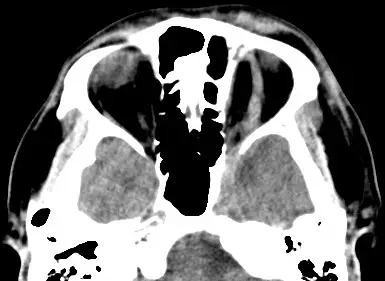

第一張影像為患者頭頸部非增強電腦斷層軸切面,可見左側眼球明顯前突(proptosis),伴隨左側 superior ophthalmic vein(SOV)擴張。眼眶內血管結構腫大及眼球向前推移符合高流量分流造成的靜脈回流受阻所致 SOV 擴張與眼眶組織充血(chemotic congestion)(ncbi.nlm.nih.gov)。第二張影像為數位減影血管攝影(DSA),可見頸內動脈海綿竇段(cavernous ICA)異常動靜脈連通,造影劑立即進入海綿竇及 SOV,顯示高流量、直接型 CCF 的典型徵象。